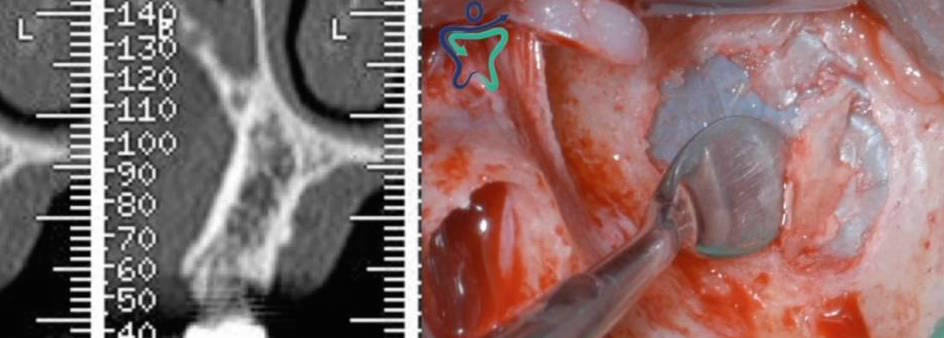

• Grande rialzo del seno mascellare con approccio laterale